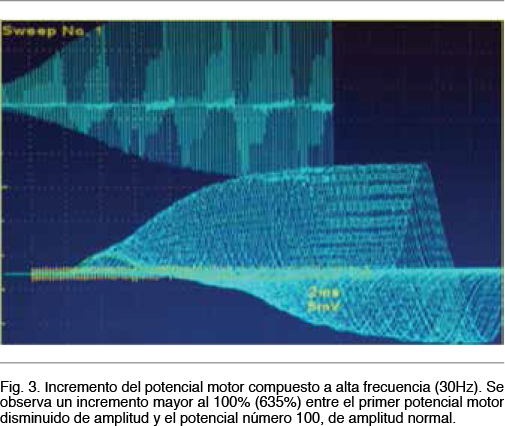

Se observa una neuroconducción sensitiva con latencias distales, amplitudes y velocidades de conducción normales. El electromiograma fue normal. Del estudio de neuroconducción motora destacamos la presencia de potenciales motores bien configurados, de latencias normales, con velocidades de conducción motora normales y sin bloqueos de la conducción, pero con amplitudes reducidas en 4 miembros. Se realiza una breve contracción isométrica de 15 segundos y se procede a la estimulación motora nuevamente, observandose un incremento de la amplitud a rangos normales. El incremento de amplitud obtenido fue > 100% para nervio motor Mediano (Figura 1). En el estudio de transmisión neuromuscular repetitiva realizado en el nervio motor Cubital se observa un decremento en el tren de potenciales obtenidos a baja frecuencia (5Hz) en un 33% entre el primer potencial y el cuarto potencial y con una morfología del tren en descenso lineal (Figura 2). El cociente de decremento tardío / decremento temprano fue de 102%. A alta frecuencia (30Hz) se observo un incremento de la amplitud de un 635% entre el primer potencial y el potencial número 100 (Figura 3).